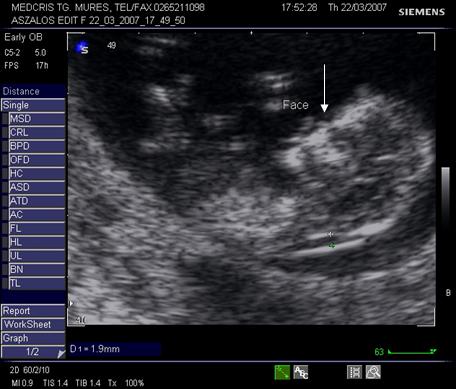

Fig. nr. 24. Profil fetal la aceeasi sarcina de 11 sapt., se remarca pliul nuchal , situat deasupra si separat de amniosul marcat cu sageata